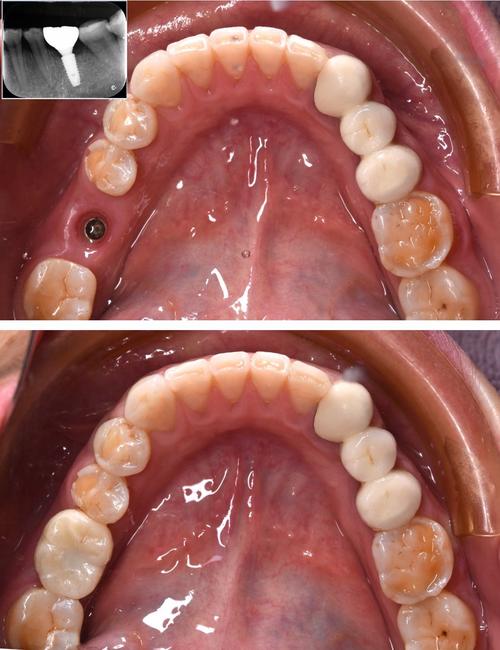

- 缝合与愈合:冲洗术区,分层缝合牙龈,拍摄X光片确认种植体位置,术后无需住院,24小时内避免刷牙漱口,遵医嘱服用抗生素预防感染。

种植体植入后需与牙槽骨发生“骨结合”(osseointegration),即种植体表面与骨组织形成牢固的骨性结合,这是种植体长期稳定的关键,上6因受力大,骨结合时间通常为3-6个月:若牙槽骨条件良好,3个月左右即可;若骨量不足需植骨,则需6个月或更长时间,期间需避免种植体受力,暂不佩戴临时修复体。